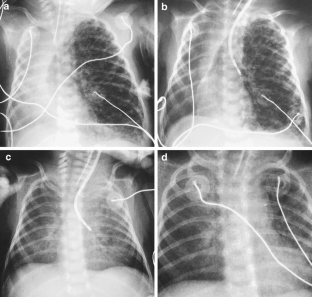

Fig. 1